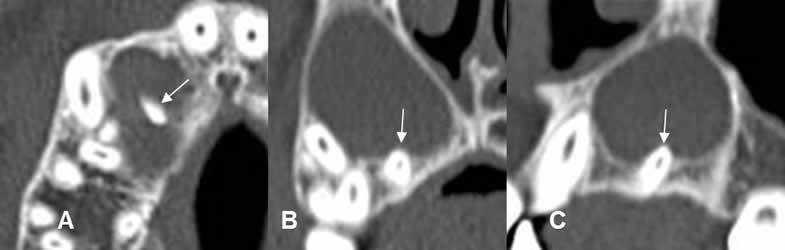

Fig 50. Periodontitis apical crónica.

A: TAC axial, B: TAC reconstrucción coronal y C: TAC reconstrucción sagital. Dilatación del espacio periapical, con la punta de la raíz en el centro de la lesión, por quiste radicular.